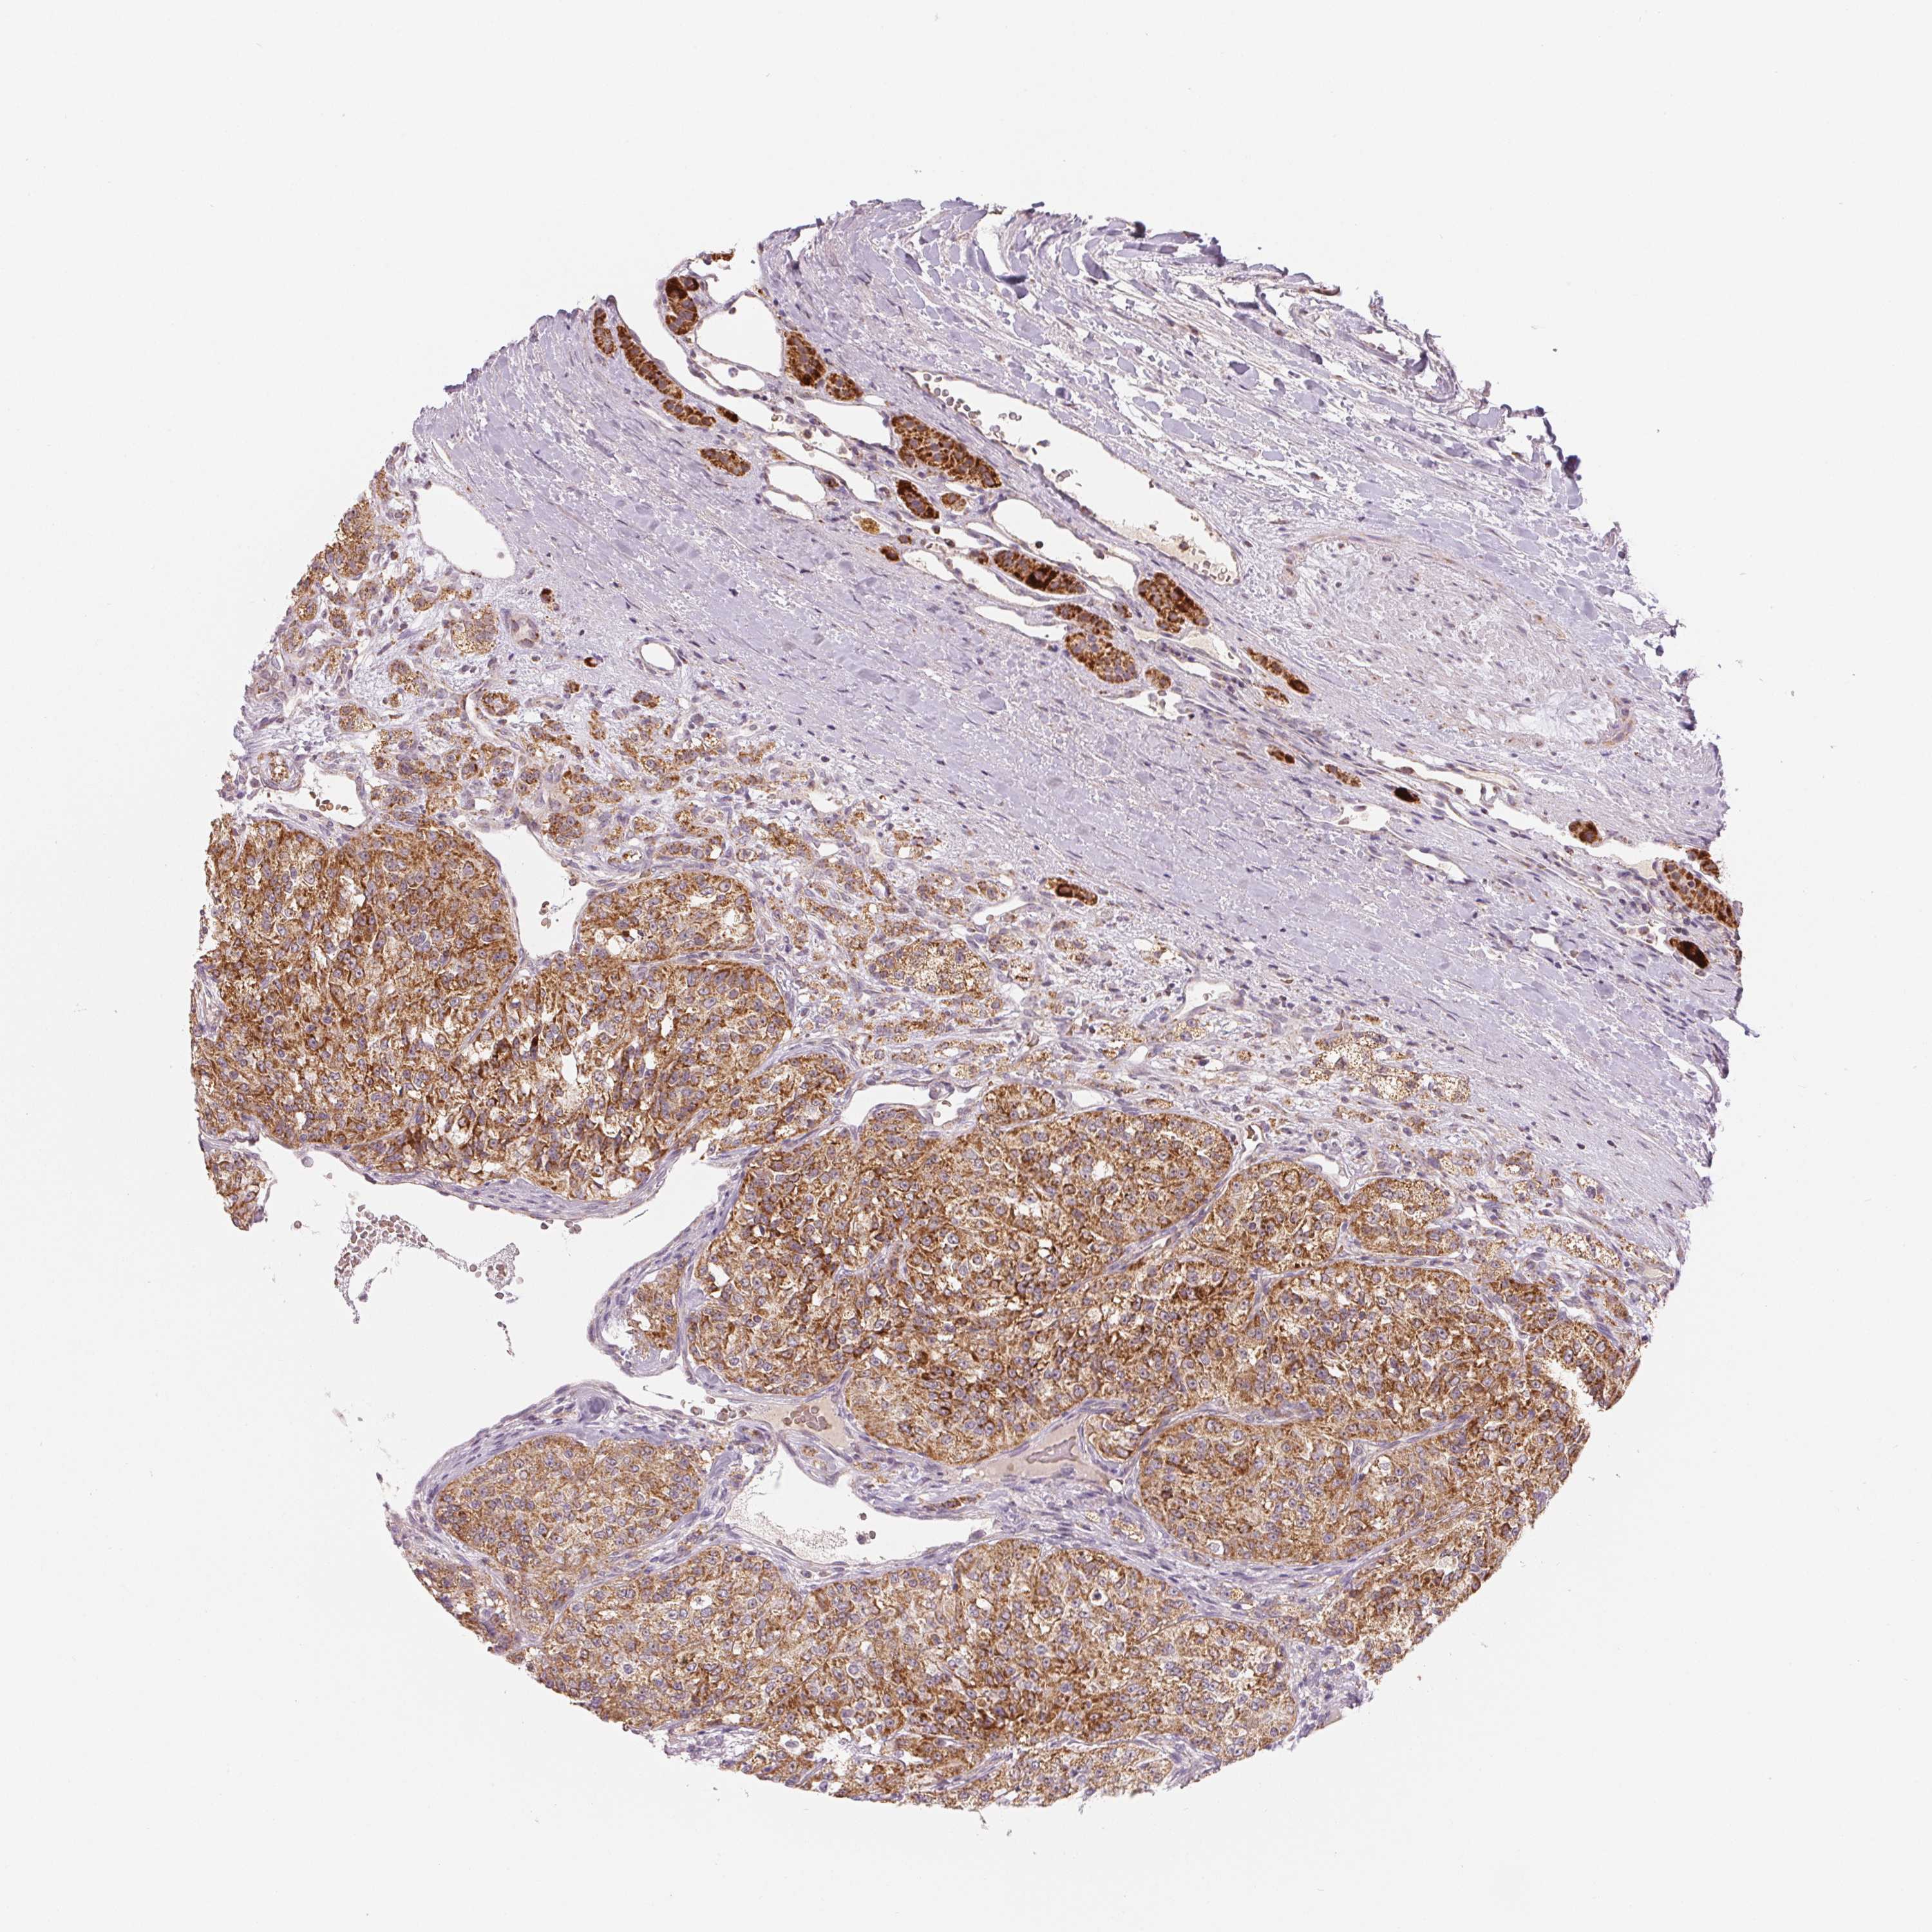

KIDNEY RENAL CLEAR CELL CARCINOMA (TCGA) - Interactive survival scatter ploti

The Survival Scatter plot shows the clinical status (i.e. dead or alive) for all individuals in the patient cohort, based on the same data that underlies the corresponding Kaplan-Meier plots. Patients that are alive at last time for follow-up are shown in blue and patients who have died during the study are shown in red.

The x-axis shows the expression levels (FPKM) of the investigated gene in the tumor tissue at the time of diagnosis. The y-axis shows the follow-up time after diagnosis (years). Both axes are complimented with kernel density curves demonstrating the data density over the axes. The top density plot shows the expression levels (FPKM) distribution among dead (red) and alive patients (blue). The right density plot shows the data density of the survived years of dead patients with high and low expression levels respectively, stratified using the cutoff indicated by the vertical dashed line through the Survival Scatter plot. This cutoff is automatically defined based on the FPKM cutoff that minimizes the p-score. The cutoff can be changed by dragging the vertical line or by entering a cutoff value in the square labeled "Current cut-off".

Under the Survival Scatter plot the p-score landscape (black curve; left axis) is shown together with dead median separation (red curve; right axis). Dead median separation is the difference in median mRNA expression between patients who have died with high and low expression, respectively. It is calculated as follows: median FPKM expression of dead patients with high expression - median FPKM expression of dead patients with low expression. This is intended to aid the user in visually exploring custom cutoffs and the associated p-scores and dead median separation.

Individual patient data is displayed and can be filtered by clicking on one or more of the category buttons on the top of the page. Categories describing expression level and patient information include: high, low, alive, dead, female, male and tumor stages. The scale of the x-axis can be toggled between linear and log-scale by clicking on the "x log" button. Mouse-over function shows TCGA ID, patient information and mRNA expression (FPKM) for each patient.

& Survival analysisi

Kaplan-Meier plots summarize results from analysis of correlation between mRNA expression level and patient survival. Patients were divided based on level of expression into one of the two groups "low" (under cut off) or "high" (over cut off). X-axis shows time for survival (years) and y-axis shows the probability of survival, where 1.0 corresponds to 100 percent.

HINT2 is potential prognostic, high expression is favorable in Kidney Renal Clear Cell Carcinoma (TCGA)

Best expression cut offi

Based on the FPKM value of each gene, patients were classified into two groups and association between prognosis (survival) and gene expression (FPKM) was examined. The best expression cut-off refers the FPKM value that yields maximal difference with regard to survival between the two groups at the lowest log-rank P-value. Best expression cut-off was selected based on survival analysis .

When clicking on this number, the vertical dashed line indicating cut-off, the interactive survival plot, and the Kaplan-Meier curve will be adjusted to show results based on the best expression cut-off.

: 36.64

TCGA RNA samplesi

RNA-seq data is reported as average FPKM (number Fragments Per Kilobase of exon per Million reads), generated by the The Cancer Genome Atlas (TCGA) .

Normal distribution across the dataset is visualized with box plots, shown as median and 25th and 75th percentiles. Points are displayed as outliers if they are above or below 1.5 times the interquartile range. FPKM values of the individual samples are presented next to the box plot.

Average pTPM 53.1

Number of samples 521